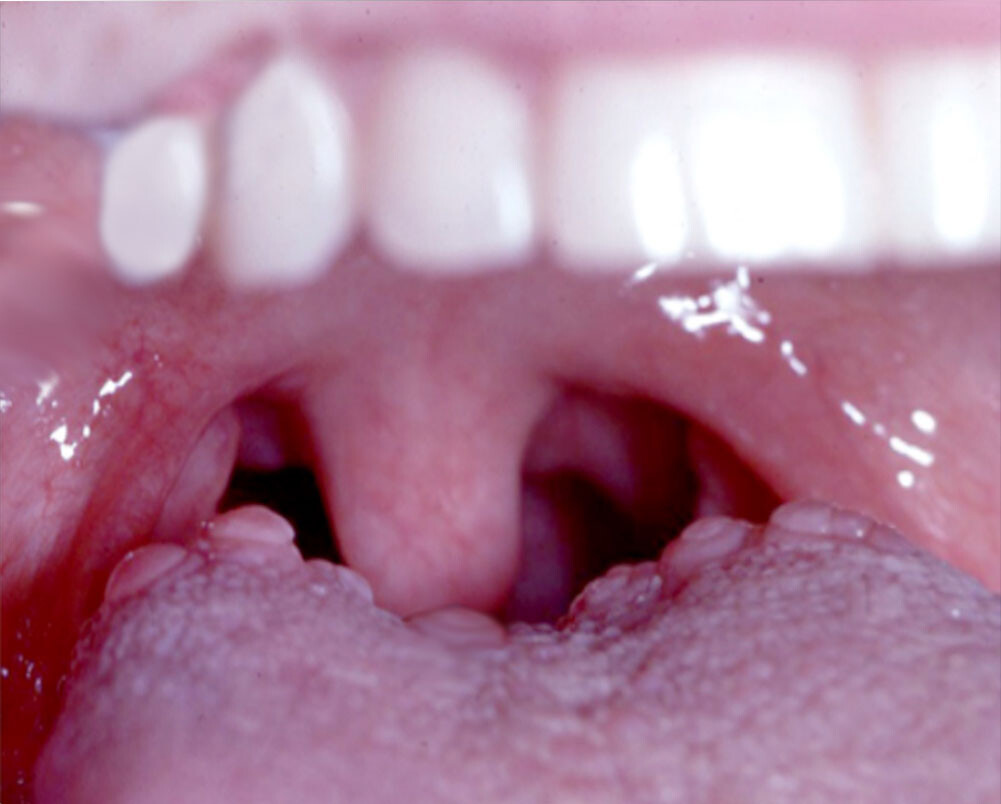

Bumps on the Back of the Tongue: Normal or Abnormal?

We don’t often think about our tongues, but they can actually be a marker of our overall health. The tongue’s appearance can change for many reasons, many of them not too serious. Have you ever noticed bumps on the back of your tongue? Often these bumps are caused by some type of oral infection. Find out what causes these bumps and when they are a cause for concern.

What Are Tongue Bumps?

The tongue is made up of muscles and the surface is covered with a mucous membrane. Typically, small bumps (also known as papillae) cover the surface of the back part of your tongue. Between the papillae are your taste buds that help you taste foods. Usually, these papillae are pretty unnoticeable. But sometimes, they become enlarged and can cause you pain. This can happen for many reasons.

What Are Common Causes of Bumps at the Back of the Tongue and How Can You Treat Them?

Some common reasons why you see large bumps at the back of your tongue include:

Oral thrush. If the inside of your mouth is red and you see white patches on your tongue and inner cheeks, you might have oral thrush. Wiping these patches off can leave red spots that bleed. The good news is that oral thrush is pretty harmless for most people and can be cured with antifungal medicine. However, oral thrush can be more serious for people with lower immunity, such as people experiencing cancer treatment or HIV/AIDS.

Leukoplakia. The primary symptom of this condition is thickened, white patches on your tongue, gums, bottom of the mouth, and the insides of your cheeks. They can’t be scraped off. Chronic irritation from tobacco is often the cause. While leukoplakia patches are usually noncancerous, some do show early signs of cancer. So, if you’re noticing these patches, it’s best to consult with your dentist or doctor as soon as possible.

Cold sores. Also known as fever blisters, these sores are caused by the herpes simplex virus (HSV) and can appear on your lips, inside your cheeks, or on your tongue. They begin as a fluid-filled blister that ruptures after a day or two before starting to heal. The sores usually last around 8-10 days and are highly contagious. Avoid oral contact — like kissing — during this time, and do not share utensils, lip balms, or other items that have touched your mouth. Cold sores usually heal on their own, and though you might be able to speed up the process with antiviral medications or creams, there is no way to get rid of HSV.

Scarlet fever. One of the symptoms of scarlet fever is a red and bumpy (“strawberry”) tongue. It’s usually accompanied by a very red, sore throat, high fever, red skin rash, and the skin in the creases of your underarm, elbow, and groin turning bright red. Scarlet fever most often occurs in children or adults who are in contact with children. Bacteria called group A strep causes this condition, and your doctor will usually prescribe antibiotics to help get rid of the bacteria.

Oral squamous papilloma. This is a benign mass that appears on the border of the tongue. They are often attributed to the human papillomavirus (HPV). According to a study in the International Journal of Scientific Reports, the best way to remove them is through surgery. They’re also unlikely to recur, except in immunocompromised patients.

Tongue cancer. Rarely, bumps on the tongue can be an indication of oral cancer. However, according to Cedars-Sinai, the lump is most likely to appear on the side of the tongue that touches the teeth. But the lump can appear on any portion of the tongue, and lumps on the base of the tongue are often hard to diagnose until they become larger. Early detection is critical here, so you must make an appointment with your doctor if you notice a lump of any size on your tongue. The lump will need to be biopsied, and your doctor will likely refer you to an oncologist.

If your notice tongue bumps at the back of your mouth, it’s normal to be worried. But the good news is that most bumps on your tongue aren’t a cause for too much concern. That said, if your bumps are large, last for several weeks, or are exceptionally painful, don’t hesitate to get them checked. Your doctor or dentist can help you feel comfortable again in no time!